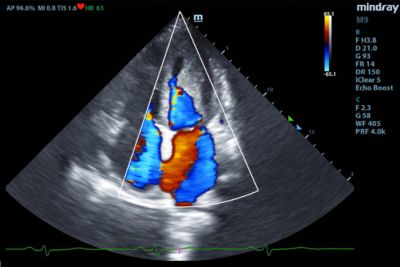

Two-dimensional transthoracic echocardiography was performed on a Mindray M9 ultrasound machine using monocrystal sector SP5-1s transducer. The examination revealed a 20 mm thick hyperechoic mass in the left ventricular (LV) cavity, closely associated with the inferior and inferolateral segments of the LV myocardium. This mass involved the posteromedial papillary muscle, posterior mitral valve leaflet and caused moderate mitral regurgitation. (Figure 1,2).

Fig. 2 - Mitral and tricuspid regurgitations.

A slight dilatation of both atria, moderate tricuspid regurgitation, overload, and decreased contractility of the right ventricle (TAPSE = 12), moderate pulmonary hypertension (Figure 3), and restrictive transmitral blood flow (Figure 4) were also detected. LV ejection fraction (EF) was preserved (65%).